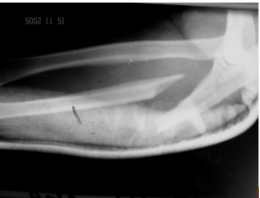

Tipo de fractura de esta rx

Essex Lopresti

Tres elementos

1. Fractura de cabeza de radio

2. Rotura de membrana interosea (migra distalmente)

3. luxacion de articulacion radio-cubital distal

Mecanismo de accion de esta fractura

Carga axial

Tratamiento de esta fractura

Reparacion o sustitucion de cabeza radial